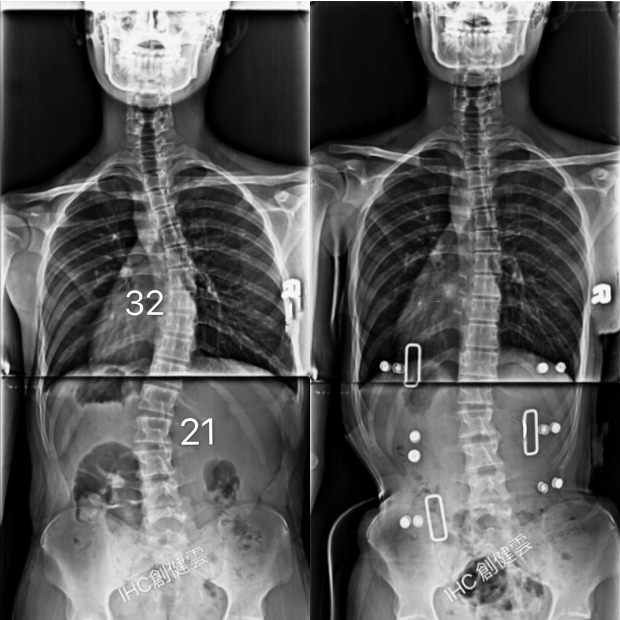

15歲脊椎側彎男孩

胸彎32度,腰彎21度